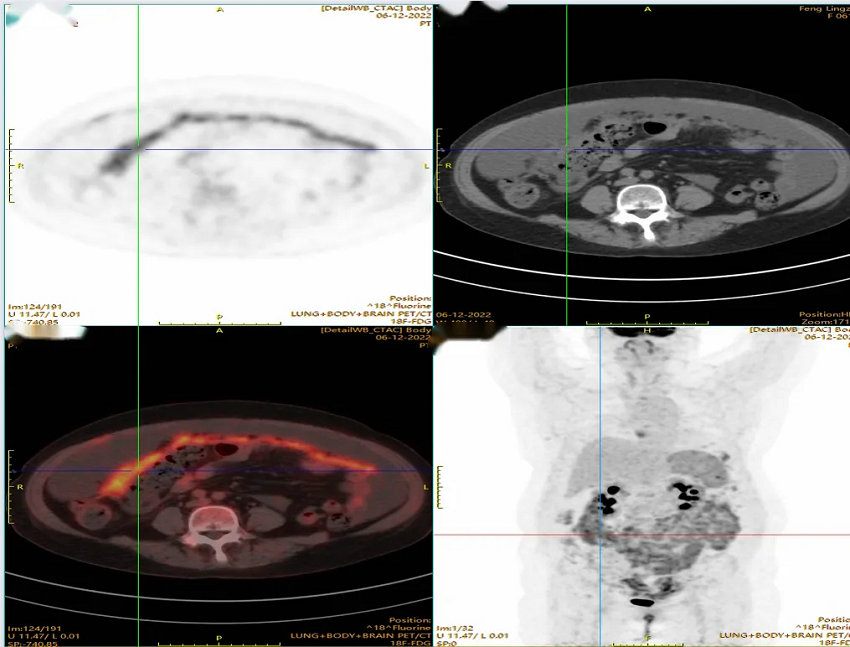

医学影像科医师李元通向大家汇报了全身PET的典型病例,通过展示病例图像、介绍病例病史、临床诊断、病检结果、随访情况等方式进行了生动的讲解和评价,临床各位主任对其所治疗的病人的临床资料及随访做进一步分享,对疾病的发生机制及变化过程,图像相应的改变进行深入解剖、分析原因,总结经验。讨论环节大家各抒已见,踊跃发言,学习氛围活跃进一步充分肯定了PET/CT在肿瘤治疗疗效评估中的不可替代的重要价值。